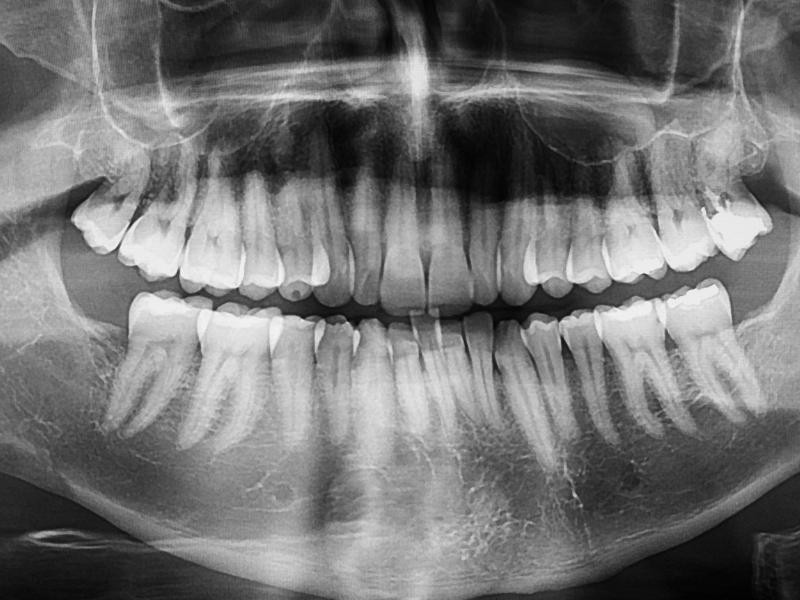

A radiografia panorâmica digital é um exame de imagem bidimensional que captura toda a boca em uma única tomada. Ele mostra todos os dentes da arcada (inclusive aqueles que ainda não nasceram, como os sisos), as articulações da mandíbula (ATM) e a estrutura óssea ao redor.

Diferente das radiografias antigas que usavam películas de filme e produtos químicos, o sistema eletrônico utiliza sensores avançados que enviam a imagem capturada instantaneamente para a tela do computador. Isso permite ao cirurgião-dentista ampliar a foto, ajustar o contraste e analisar detalhes anatômicos com clareza.

O exame de raio-x panorâmico digital é o ponto de partida seguro para qualquer tratamento odontológico. Ele oferece uma visão ampla e detalhada de todos os dentes, raízes e ossos faciais em apenas alguns segundos.

Permite observar a relação exata entre as raízes, os nervos faciais e a densidade do osso maxilar de uma só vez.